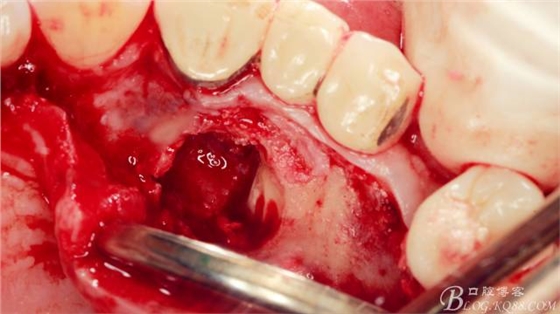

局麻下做齦溝內(nèi)切口

翻瓣,長柄球鉆清掃薄薄的骨皮質(zhì),暴露出牙冠,動(dòng)作一定要輕柔,感覺就像在雞毛撣子一樣撣花瓶上的灰一樣,因?yàn)楣呛脱烙再|(zhì)有明顯的密度差異,手感上面差別比較明顯。

長柄裂鉆分離牙冠,微創(chuàng)挺插入后順時(shí)針或者逆時(shí)針輕擰一下,手上去感受牙冠斷開的那一瞬間,有時(shí)候耳朵也能聽見啪得一聲,不過此刻因?yàn)檠拦谥車墓亲枇?,牙冠是不能取出的?p style="text-align: left;">

T形分牙,把牙冠分為兩瓣,減少阻力。

分別挺出兩瓣牙冠,可見牙根截?cái)嗝妗?p style="text-align: left;">

微創(chuàng)挺直接挺出牙根。

取出牙根,清理創(chuàng)面。

縫合。